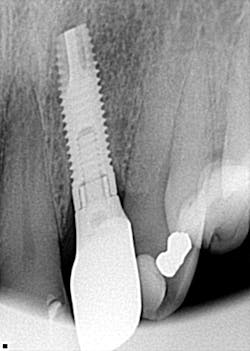

CAN YOU REALLY IDENTIFY more than 900 dental implants by looking at a single radiograph? I got my answer to this question when a patient came in and needed his lower fixed hybrid prosthesis removed. That bad boy had been on there for a long time and was, quite frankly, nasty! The problem? There was no record of who placed the implants or which dental implant system was in place. What did I do? Well, what do others do when they are faced with the same dilemma? You can read about it at this link; you may be surprised at just how much information a single radiograph can give you!

In our pathology case this month, a patient presents with a big “black hole” in her right mandible. It hurts, and it’s clear that some crazy sort of pathology is having its way. Take a look at this radiograph and ruminate over what you’d do to get this patient taken care of.